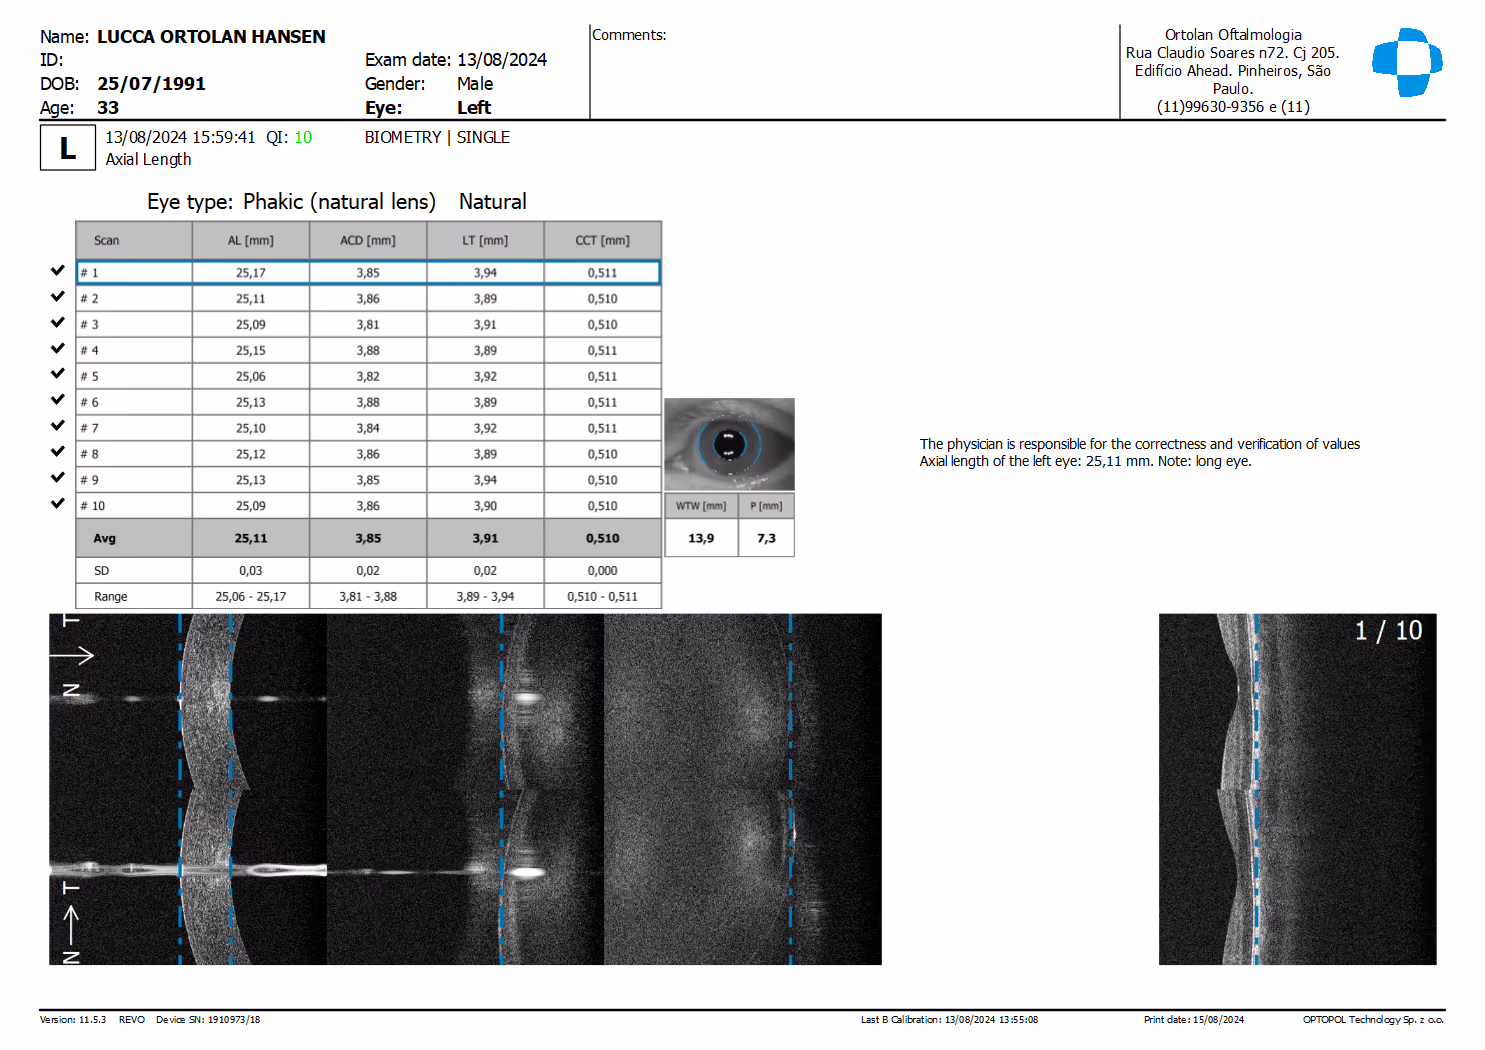

No segmento anterior, o OCT avalia a espessura da córnea, o perfil de cicatrização pós-LASIK/PRK, planejamento de ICL (distância entre o endotélio e o cristalino), posicionamento de tubos de glaucoma e profundidade da câmara anterior em olhos com risco de fechamento angular.